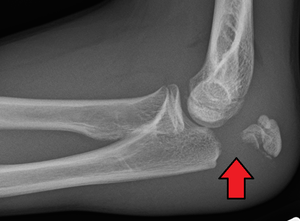

Olecranon fracture is a fracture of the bony portion of the elbow. The injury is fairly common and often occurs following a fall or direct trauma to the elbow. The olecranon is the proximal extremity of the ulna which is articulated with the humerus bone and constitutes a part of the elbow articulation. Its subcutaneous location makes it vulnerable to direct trauma. Powerful pull of the triceps muscle can also cause avulsion fractures.

People with olecranon fractures present with intense elbow pain after a direct blow or fall. Swelling over the bone site is seen and an inability to straighten the elbow is common. Examination brings out a palpable defect indicating a displaced fragment or a comminuted fracture.

Direct trauma: This can happen in a fall with landing on the elbow or by being hit by a solid object. Trauma to the elbow often results in comminuted fractures of the olecranon.